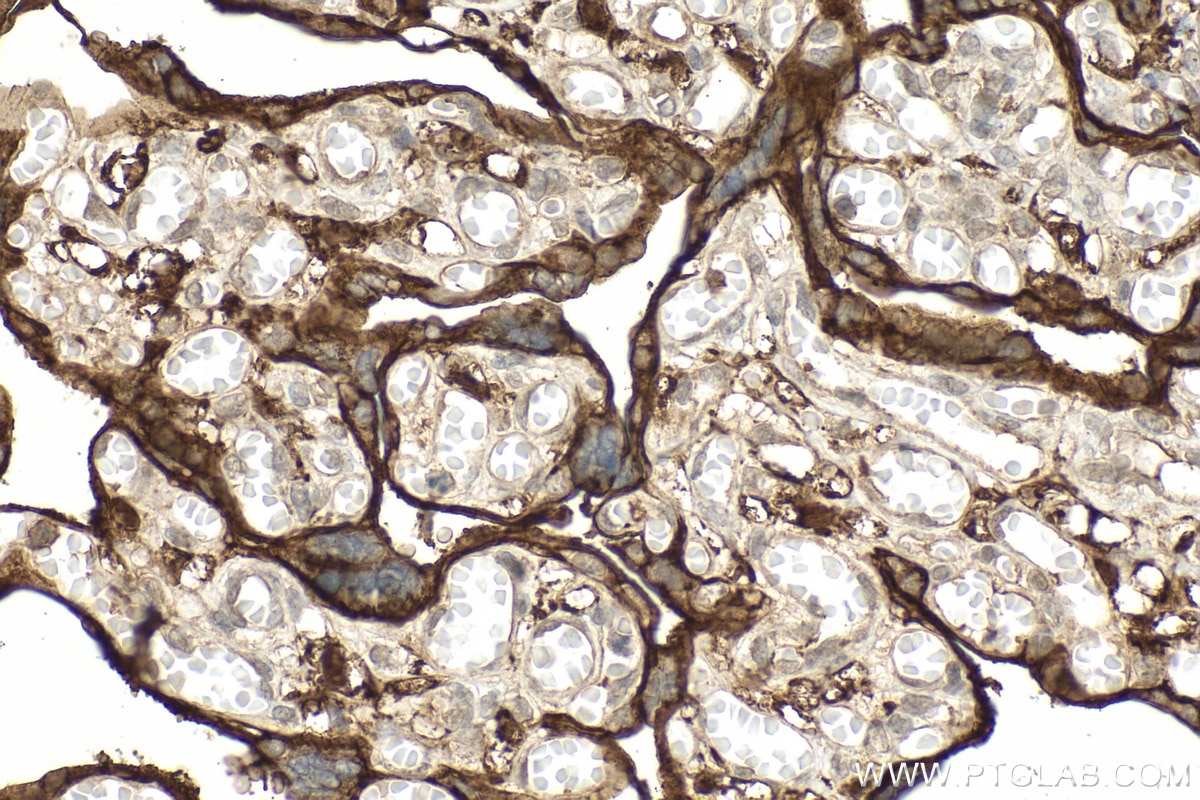

| Positive IHC detected in | human placenta tissue Note: suggested antigen retrieval with TE buffer pH 9.0; (*) Alternatively, antigen retrieval may be performed with citrate buffer pH 6.0 |

| Immunohistochemistry (IHC) | IHC : 1:200-1:800 |